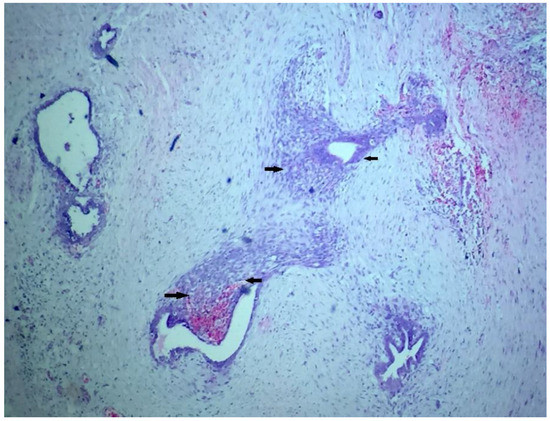

2. Case Presentation